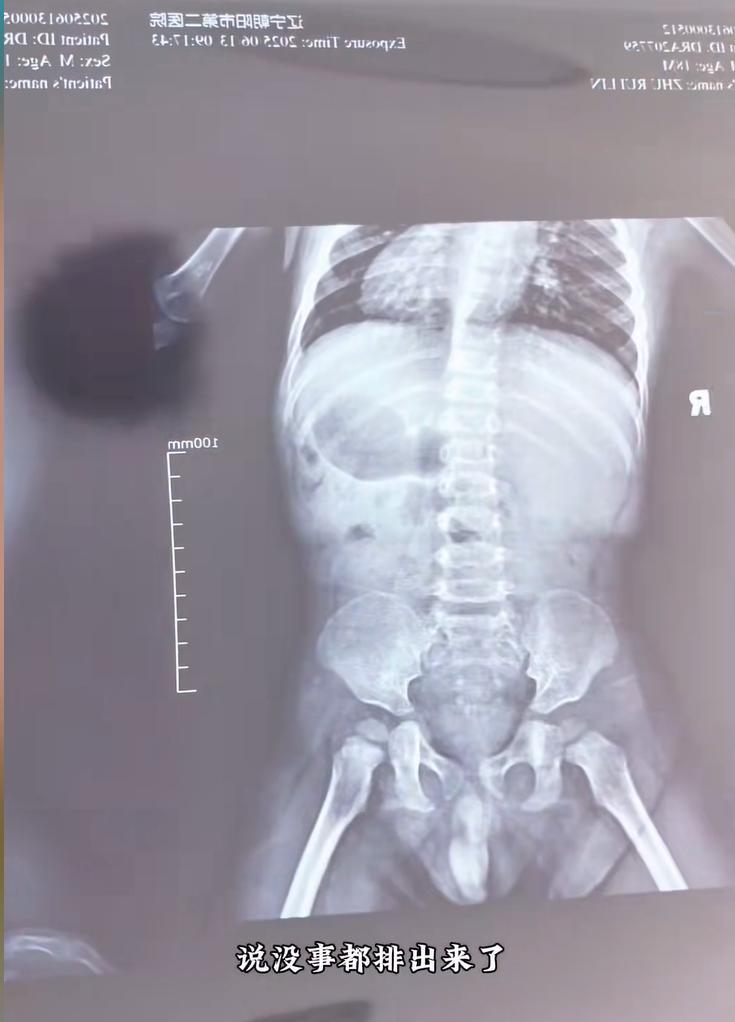

處理完現場,媽媽立刻帶着佑佑趕往醫院。醫生給孩子拍了片子,結果顯示腸道里確實有一些亮晶晶的散落陰影——正是那些水銀珠。幸好,孩子的腸道也沒有破損。

醫生解釋說:水銀中毒主要是通過揮發後的蒸氣,經呼吸道吸入引起的。 如果體溫計裏的液態水銀進入腸道,只要腸道沒有傷口,一般不會被吸收,問題不大。

片子裏的亮晶晶的東西就是水銀珠,回去後讓孩子多喫多喝,特別是富含膳食纖維的食物,比如火龍果、西梅、韭菜、黑木耳等,促進腸道蠕動,水銀就能隨着糞便排出來。

佑佑媽媽不放心地問:“醫生,不開點藥喫嗎?”醫生回答:“這種情況一般不引起中毒,只要排出來就沒事,所以也沒什麼特效藥可治。回家就讓他多喫多喝,促排便就行。”

於是,媽媽按照醫囑,給孩子準備了韭菜餃子、青菜,又買了火龍果和西梅,讓孩子可勁兒地喫。等到第二天下午,孩子上過廁所後,媽媽又帶他去醫院拍片複查。醫生一看新片子,裏面已經基本沒有亮晶晶的陰影了,對媽媽豎起了大拇指:“處理得非常正確,執行得也很好!”